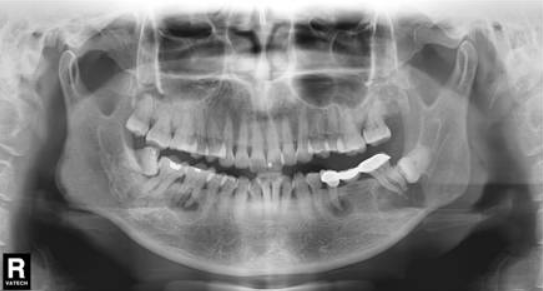

拔牙热知识:术前多读片,阻力牙才不会变压力!